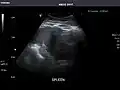

Ultrasound can also be used if there is suspicion of enlargement of one or more organs, such as used in screening for abdominal aortic aneurysm, investigation for splenomegaly or urinary retention.

In cases of infectious mononucleosis, splenomegaly is a common symptom, and health care providers may consider using abdominal ultrasonography to get insight into a person's condition.[5] However, because spleen size varies greatly, ultrasonography is not a valid technique for assessing spleen enlargement and should not be used in typical circumstances or to make routine decisions about fitness for playing sports.[5]

Spleen: Normal in size.